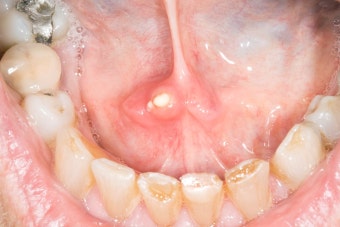

세균성 감염은 급성으로 나타나며, 갑자기 침샘이 붓고 심한 통증과 열을 동반합니다. 고름이 생기면 침을 삼킬 때 불편함이 심해지고, 심할 경우 입 안에서 고름이 배출되기도 합니다. 이런 경우엔 빠른 항생제 치료가 필요하며, 치료가 늦어지면 감염이 주위 조직으로 퍼져 더욱 위험한 상태가 될 수 있습니다.

특히 감염성 원인일 경우엔 열과 함께 박동성 통증이 느껴지고, 심하면 피부까지 화끈거리는 느낌이 듭니다. 세균 감염이 있을 경우 고름이 차면서 입 안에서 고름이 배출되기도 합니다. 반대로 쇼그렌 증후군처럼 만성 자가면역질환에서는 붓기는 있지만 통증은 거의 없으며, 지속적인 불편함만 남는 경우도 많습니다.

보존적 치료나 약물로 효과가 없는 경우에는 외과적 치료가 필요합니다. 세균 감염으로 인해 고름이 차면 절개 및 배농술을 시행해야 하며, 이를 통해 감염된 고름을 제거하고 염증을 완화할 수 있습니다. 보통 국소마취 하에 간단히 시행되며, 이후에는 항생제를 지속적으로 복용해야 합니다.

- 침샘 부위에서 고름이 나오거나, 입에서 고약한 냄새가 날 때